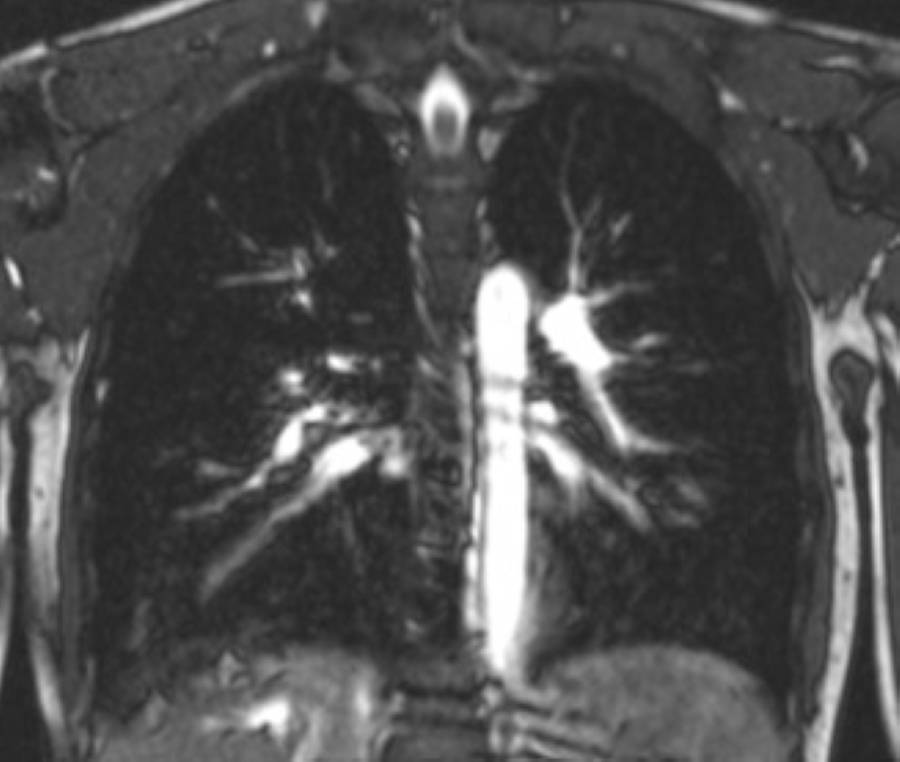

Eine Magnetresonanztomographie des Brustkorbs, kurz die MRT Thorax genannt, ist ein medizinisch bildgebendes Verfahren. Die MRT Thorax Untersuchung stellt mithilfe von Magnetfeldern und Radiowellen insbesondere die Lungenflügel, das Herz, die großen Blutgefäße und das Mediastinum detailliert dar. Vor allem bei Verdacht auf Tumore oder andere komplexe Erkrankungen im Brustbereich kann eine MRT Thorax aufschlussreich sein.

Bei der Thorax MRT-Untersuchung wird ein Hochfrequenzsystem verwendet, das die Ausrichtung dieser Atomkerne ändert. Während die Kerne in ihre ursprüngliche Position zurückkehren, senden sie Signale aus. Diese Signale werden von speziellen Detektoren aufgefangen und in Bilder umgewandelt. Das Ergebnis sind detaillierte Querschnittsbilder des Brustkorbs, die es ermöglichen, die inneren Strukturen wie Lungen, Herz, große Blutgefäße und das Mediastinum in hoher Auflösung darzustellen.

Verdacht auf Mediastinaltumor: Das Mediastinum ist der Raum zwischen den Lungenflügeln, in dem sich das Herz, große Blutgefäße und andere wichtige Strukturen befinden. Tumoren in diesem Bereich können durch eine MRT präzise lokalisiert und charakterisiert werden.

Verdacht auf Pancoast-Tumor: Dieser spezielle Typ eines Bronchialkarzinoms befindet sich an der Lungenspitze und kann in die umliegenden Strukturen wie Nerven und Blutgefäße einwachsen. Eine MRT hilft dabei, die genaue Ausdehnung und den Einfluss auf angrenzende Gewebe zu beurteilen.